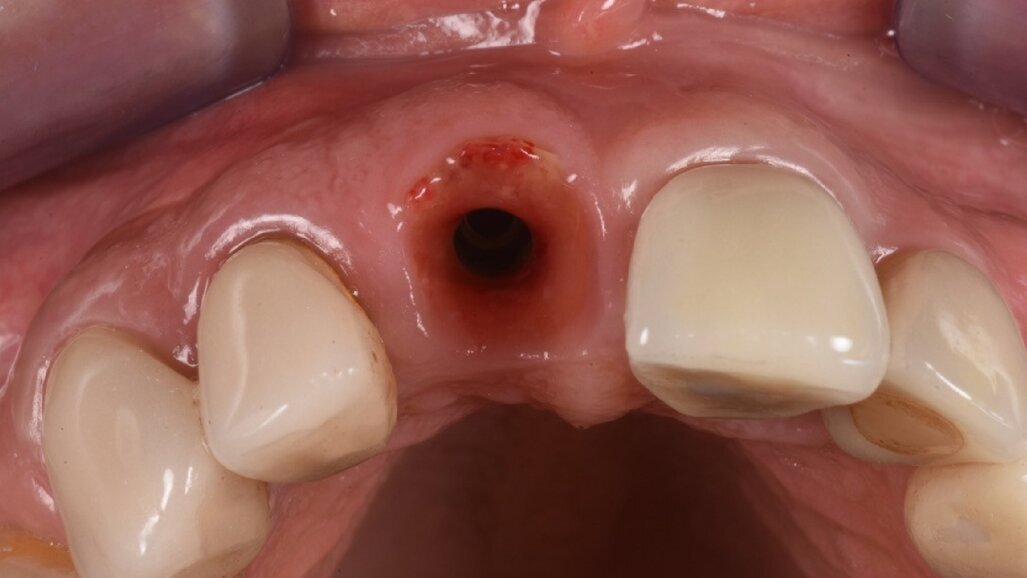

A questo punto veniva avvitato sull’impianto un moncone provvisorio, completato l’innesto di materiale biocompatibile con osso equino collagenato (OX granules, Bioteck) nel gap esistente tra la fixture e la lamina, poi veniva connessa al moncone provvisorio la corona provvisoria in resina (Fig. 13). La rx di controllo post intervento evidenzia la buona riuscita della procedura e la corretta connessione tra moncone e fixture (Fig. 14). Sei mesi più tardi alla rivalutazione e rimozione della corona provvisoria (Fig. 15) si può ben notare come questa procedura abbia permesso di mantenere integri i tessuti peri-implantari, di aver favorito la creazione di un tunnel mucoso spesso e maturo. I tessuti con e senza la corona provvisoria mostrano un aspetto naturale e le caratteristiche di una gengiva in salute (Figg. 16a, 16b).